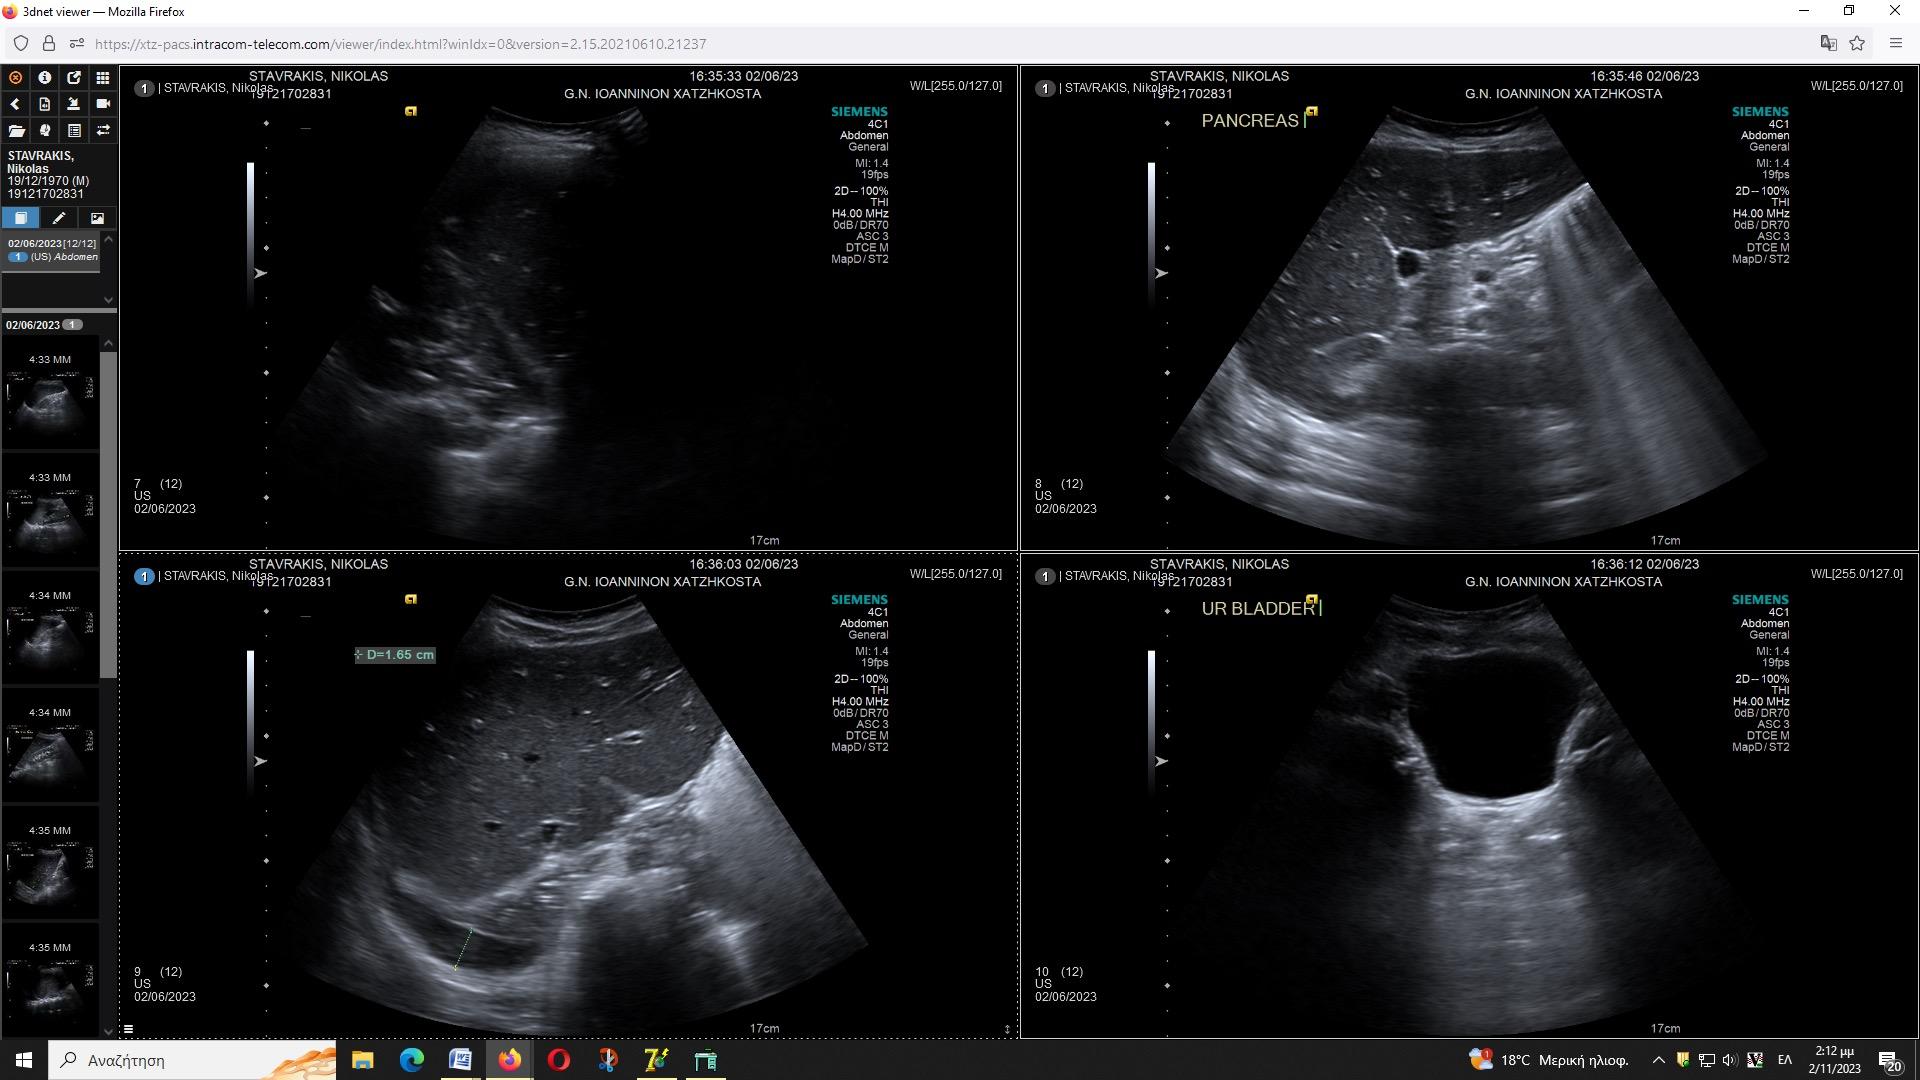

Turn static files into dynamic content formats.

Create a flipbook

Issuu converts static files into: digital portfolios, online yearbooks, online catalogs, digital photo albums and more. Sign up and create your flipbook.